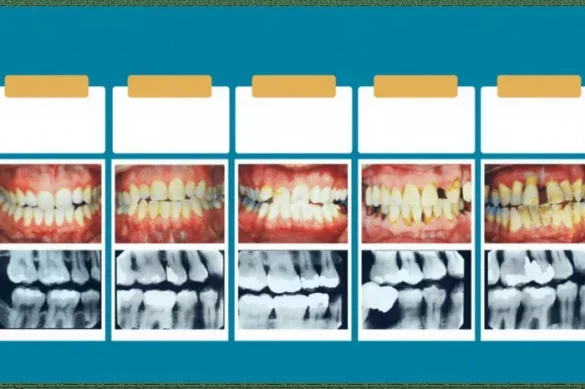

Gingivitis is the earliest stage of gum disease, formally known as periodontal disease. It occurs when the gums become inflamed due to a buildup of bacterial plaque along the gumline. This infection is common and affects millions of people. Its hallmark signs include red, swollen gums, bleeding when brushing or flossing, and sometimes bad breath. Left untreated, gingivitis can progress to periodontitis, which may cause permanent damage to the tissues and bones supporting the teeth.

The primary cause of gingivitis is plaque—a sticky film of bacteria that forms on teeth. If plaque is not removed by regular brushing and flossing, it can harden into tartar, which further irritates the gums. Initial symptoms are often mild, such as: